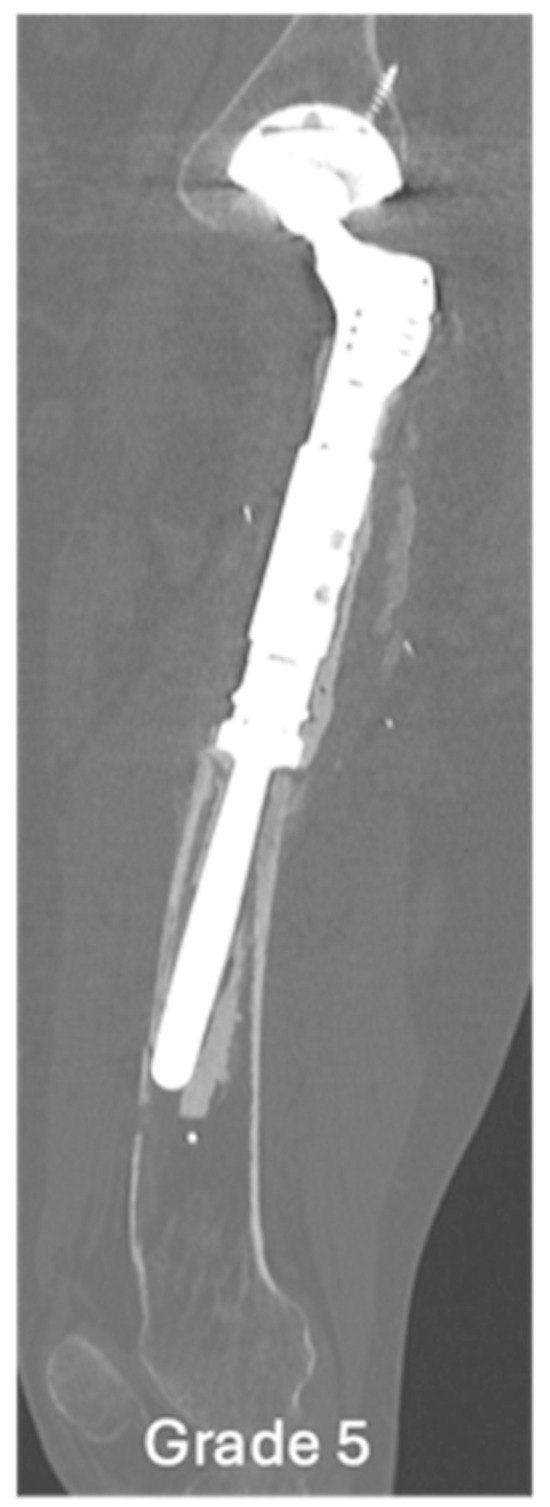

| Grade of loosening | |

| Grade 5 | 1 (3.6) |